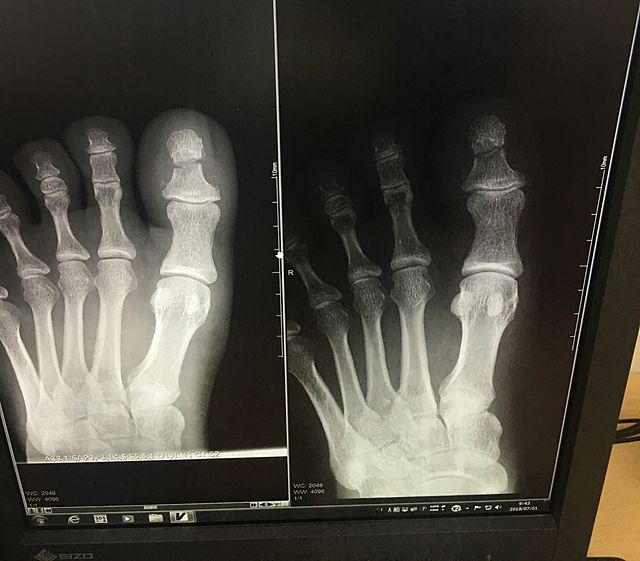

骨折なう

左足の親指を。

机を倒してしまいギロチン状態。

痛い。全治三カ月。